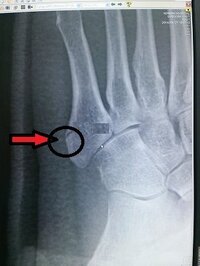

第五中足骨骨折 下駄骨折 基底部 をして 2か月経ちました 骨は綺麗 Yahoo 知恵袋

ちょっと足首を挫く、いわゆる捻挫は誰でも経験あるかと思われます。 しかし、時には単なる捻挫で済まないこともあります。 痛みや腫れが強いので病院を受診したら「骨折しています」と言われてびっくりする事態にもなります。 この骨折はその昔、下駄をはいていて挫いたとき発生しやすかったため「下駄履き骨折、または下駄骨折」という名前がついてい骨折に対する代表的な治療は以下の3つです。 外科手術 薬の服用などの内科的治療 リハビリによる機能改善、痛みの緩和、姿勢の修正 以前は、ギプスが外れてからリハビリを開始するのが一般的でしたが、近年ではできるだけ早期よりリハビリを開始するようになりました。もう早く治りますように♡って祈ってる!今ここで」 骨折「めっちゃ嬉しいです!」 遥香「本当に頑張ってほしいね~。でも今年の夏はそっか試合は厳しいそうって言ってましたよね」 骨折「はい、厳しいって言われました」 遥香「そうだよね。

第五中足骨を 骨折したんですがこれくらいだったらどのくらいで治りま Yahoo 知恵袋

第五中足骨基部骨折について 家の階段で足を挫いて 小指側を内側に向 Yahoo 知恵袋

第五中足骨を骨折しました この怪我は酷い方でしょうか 何日で治るで Yahoo 知恵袋